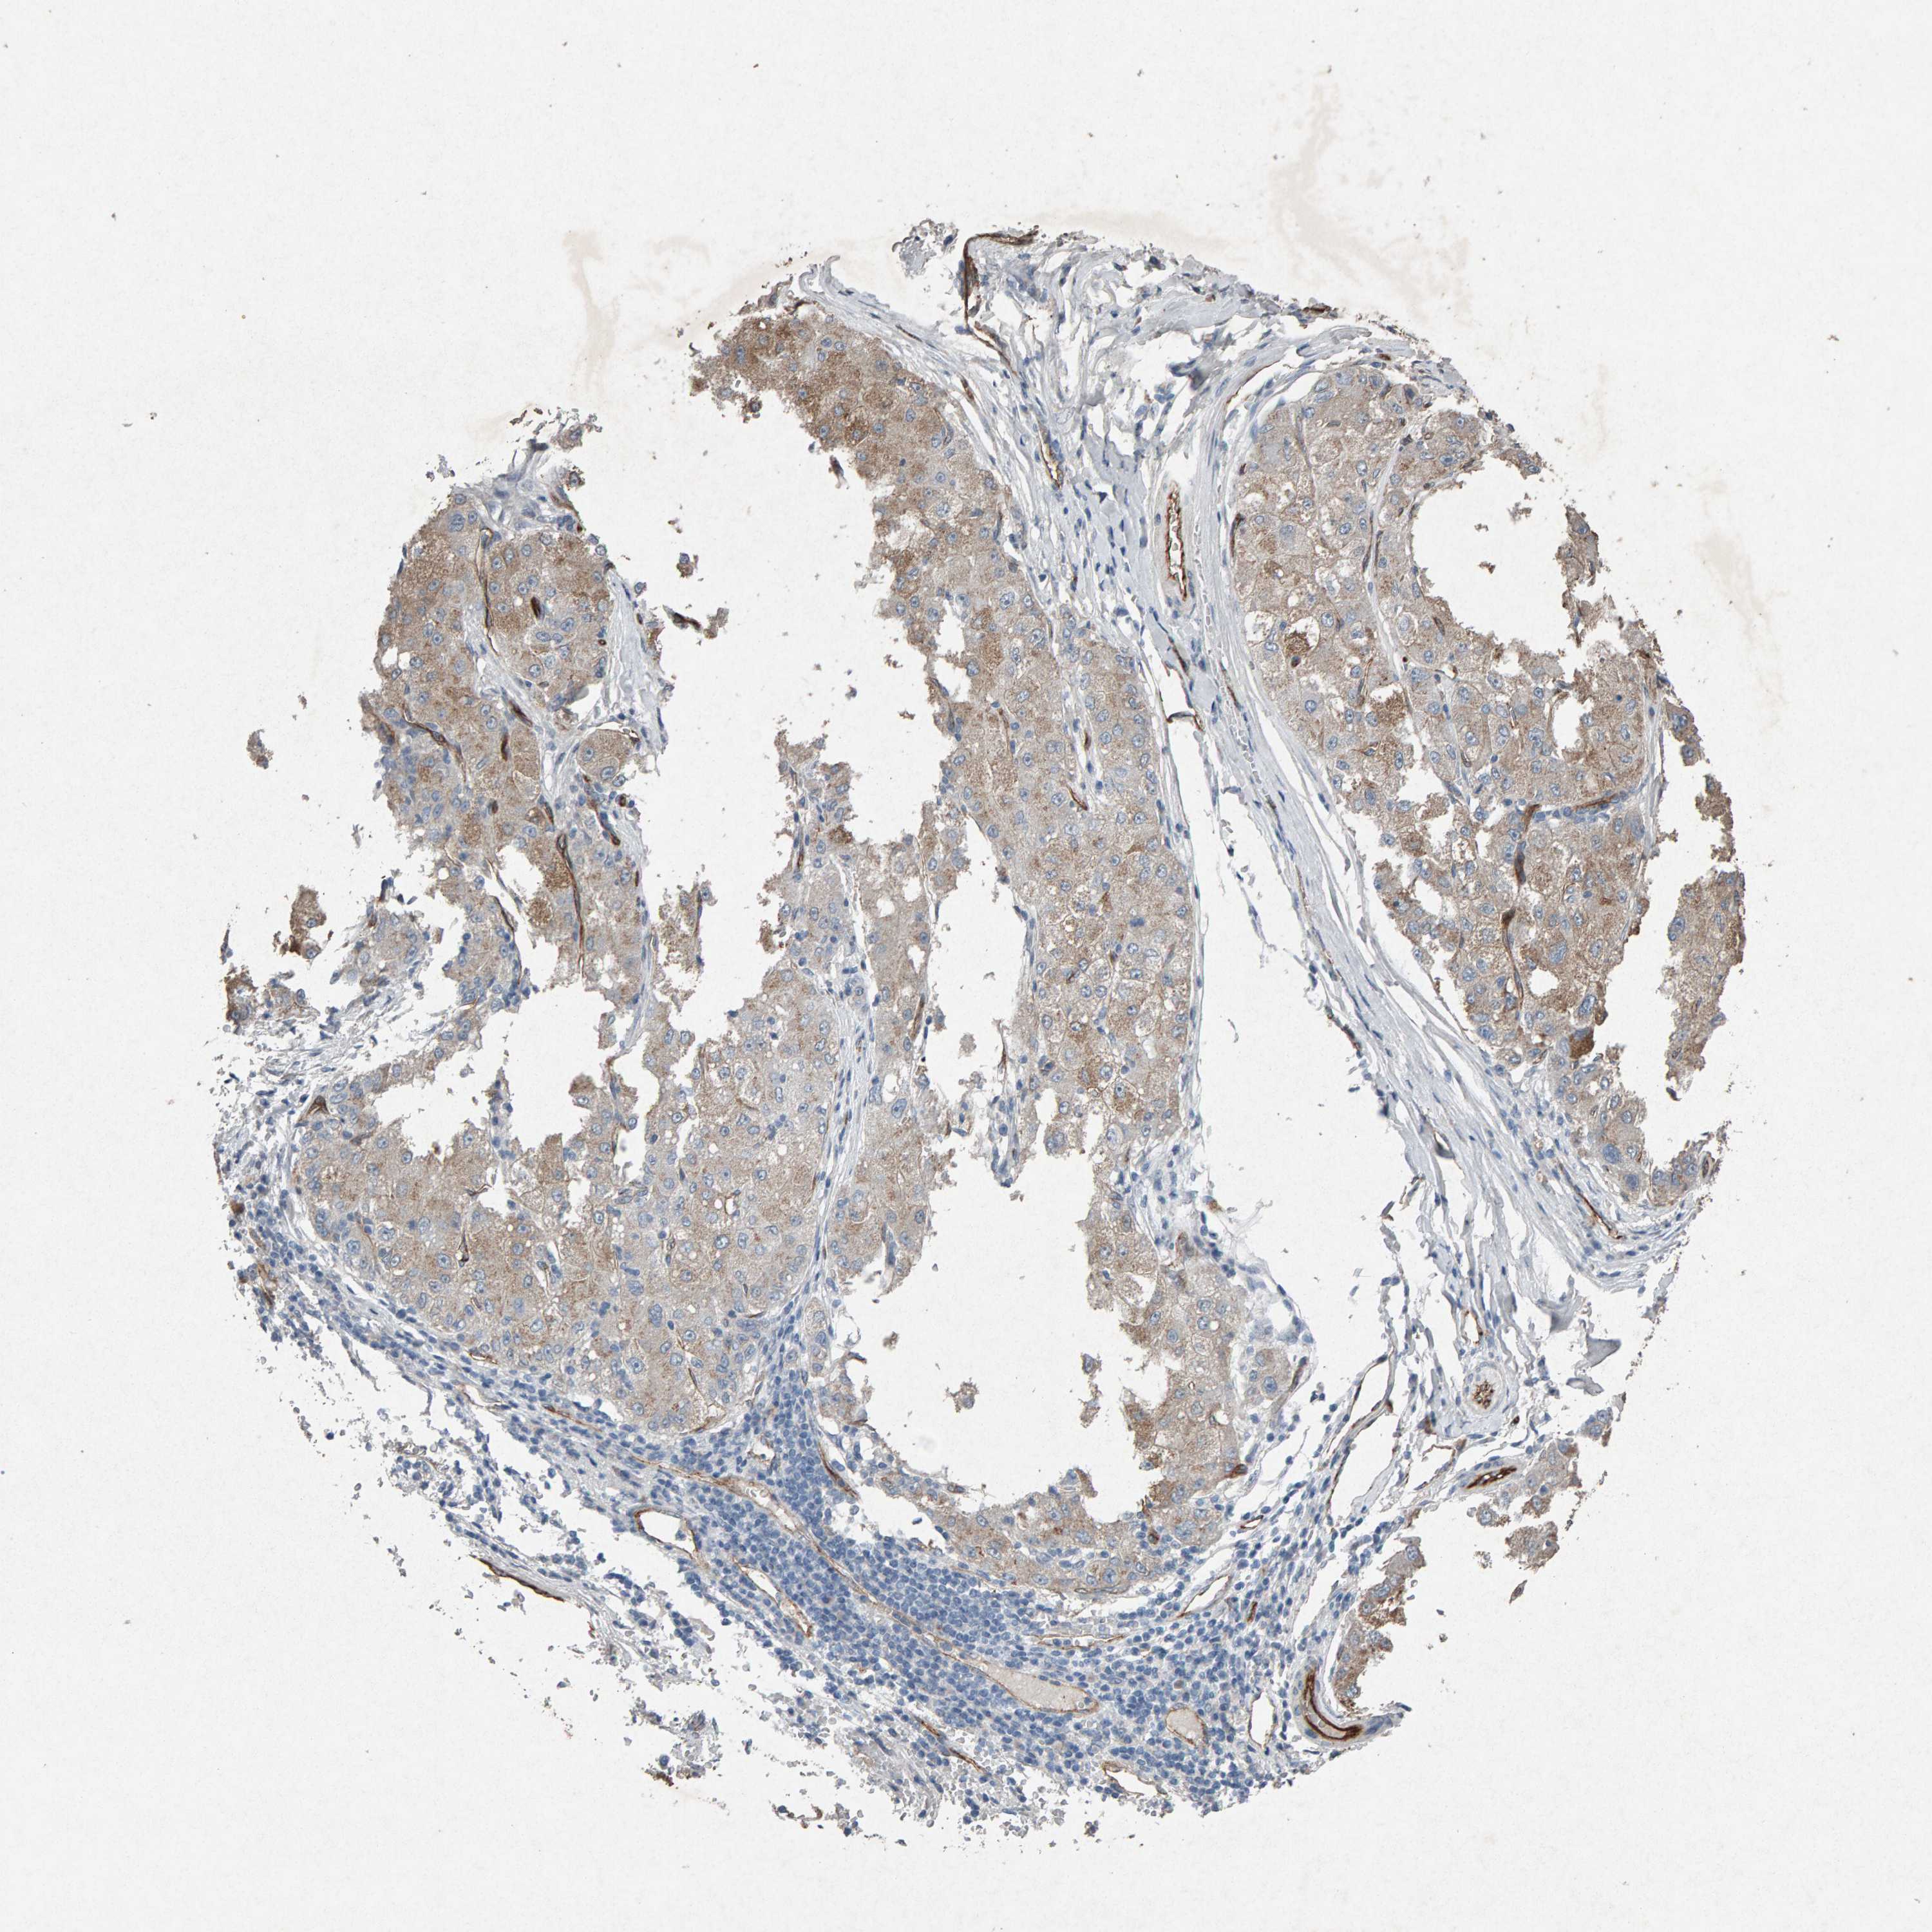

LIVER CANCER - Protein expressioni

A mouse-over function shows sample information and annotation data. Click on an image to view it in a full screen mode. Samples can be filtered based on level of antibody staining by selecting one or several of the following categories: high, medium, low and not detected. The assay and annotation is described here.

Note that samples used for immunohistochemistry by the Human Protein Atlas do not correspond to samples in the TCGA dataset.

Antibody stainingi

Antibody staining in the annotated cell types in the current human tissue is reported as not detected, low, medium, or high, based on conventional immunohistochemistry profiling in selected tissues. This score is based on the combination of the staining intensity and fraction of stained cells.

Each image is clickable and will lead to virtual microscopy that enables deeper exploration of all samples and also displays staining intensity scores, fraction scores and subcellular localization as well as patient and tissue information for each sample.

Antibody CAB022442

Antibody CAB022443

Staining

High

Medium

Low

Not detected

Intensity

Strong

Moderate

Weak

Negative

Quantity

>75%

75%-25%

<25%

None

Location

Nuclear

Cytoplasmic/membranous

Cytoplasmic/membranous,nuclear

Cholangiocarcinoma

Carcinoma, Hepatocellular, NOS